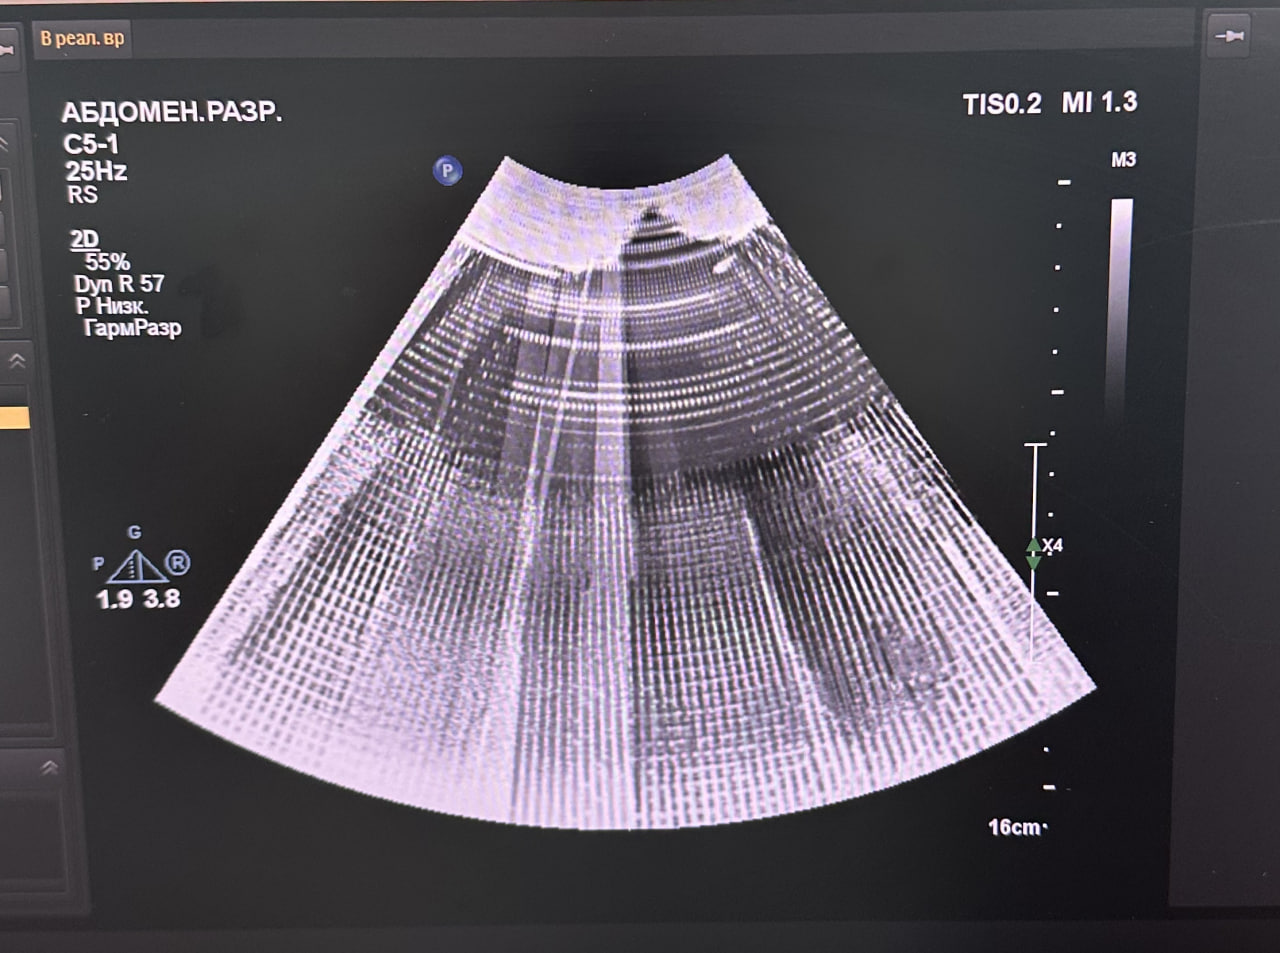

⚠️ Неисправность: При сканировании на изображении наблюдалось множество белых полос по всему экрану, визуализация была сильно искажена.

Выполнен компонентный ремонт модуля с заменой неисправных элементов. После восстановления изображение стабильное, артефакты отсутствуют. Система прошла проверку во всех режимах сканирования.